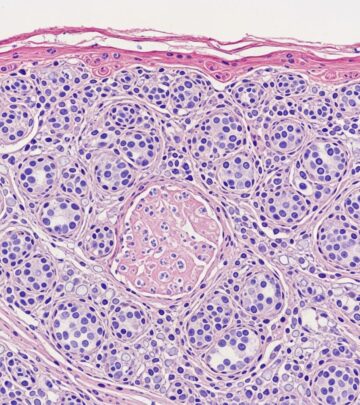

Fibrofolliculomas in Birt-Hogg-Dubé Syndrome Images